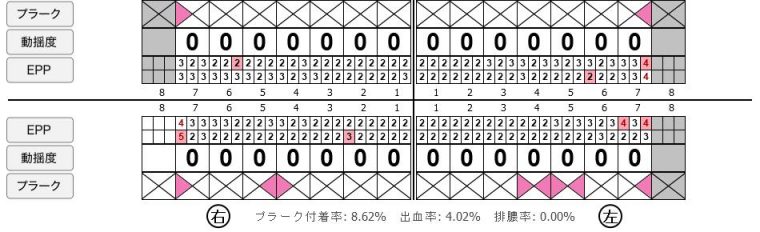

歯周病検査(治療前)

歯周病検査(治療後)

レントゲン写真

| 年齢・性別 | 32歳・男性 |

|---|---|

| 主訴 | 主訴:歯ぐきから出血する 治療部位:全顎 |

| 治療内容 | 「全顎」 歯周基本治療(歯周精密検査、スケーリング、OHI、SRP) |

| 治療期間 | 約3ヶ月 |

| 治療費 | 歯周基本検査:約600円(保険診療3割負担) スケーリング、OHI:約2,000円(保険診療3割負担)×2回 SRP、OHI:約1,500円(保険診療3割負担)×4回 歯周精密検査:約1,200円(保険診療3割負担)×2回 合計金額13,000円 (2025年2月現在) |

| リスク・副作用 | 歯石を取った後に、歯がしみることがあります。 |

| 治療方針 | ①検査 レントゲン、口腔内写真を撮影して、歯や歯周組織の状態を確認します。 また、歯周病の検査で歯周ポケットの深さや出血の有無を確認します。 ②スケーリング、OHI(口腔衛生指導) スケーリングをして歯の表面の歯石を除去します。 また、正しい歯磨きの仕方や、フロスの通し方を一緒に確認します。 ③歯周精密検査 前回歯石除去と歯磨き指導を行なった結果、歯ぐきの状態がどれぐらい改善したか検査します。 ④SRP 歯ぐきの内側についてる歯石を除去します。 ⑤歯周精密検査 SRP後、歯周病が改善されたか、検査します。 歯周ポケットが4ミリ以上の部位は、再度SRPを行います。 今回は歯周病の状態が安定したため、3ヶ月おきの定期検診で歯周病の再発や進行を防ぎます。 |

| 特記事項 | 歯周精密検査について: ・歯周ポケットが4ミリ以上ある場合は歯周病で、3ミリ以下は健康な歯ぐきです。 ・出血の有無で炎症があるか確認します。 ・磨き残しがある部分を確認して記録します。 |

| 担当者所見 | 初診時は、写真を見て分かるように、歯ぐきが赤く腫れていました。 また、歯周病の検査では、全体的に歯と歯の間の部分の歯周ポケットが4ミリあり、全体の約81%から出血が認められました。 出血量も多く、歯ぐきに触れた瞬間に出血しました。 レントゲンで骨のレベルがしっかりとあることが確認できました。 そのため、ご自身で正しい歯磨きを継続することで改善すると考えました。 歯周基本治療を経て、再度検査した結果、歯周ポケットはほぼ3ミリ以下に改善しました。左下7番の残存した歯周ポケットは、隣の親知らずを抜いたため経過観察します。 出血率は約4%まで改善し、出血量も点状で少なくなりました。 今後は右上2番、右下3番の歯ぐきの発赤の改善と、出血率0%を目指して、定期検診でメンテナンスしていきます。 |